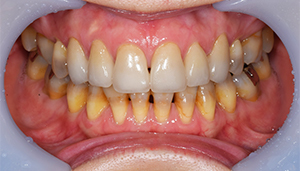

治療後:前の歯

担当医師所見:

前歯部はホワイトニング後に、仮歯に置き換え症状のないことを確認してからジルコニアボンドCrにて補綴。 審美性・機能面ともに調和がとれている。

治療前後の写真

治療前

治療後

年齢・性別 30代・男性

主訴 奥歯が痛くて噛めない

治療期間 半年間

治療費 合計:1,595,000円 (内訳)

・左上567ジルコニアブリッジ: 110,000×3本

・右下567ジルコニアブリッジ: 110,000×3本

・右上6ジルコニアクラウン:110,000×1本

・左下6、右上45セラミックインレー:55,000×3本

・上顎前歯部: 165,000×4本

治療方針 ・保存不可能な歯の抜歯

・歯周病治療

・根管治療(歯の根っこの治療)

・虫歯治療

・審美治療

治療内容 ・抜歯:右下第1大臼歯はCT撮影後歯根破折を認めた。また左上第一大臼歯は残根(根っこだけ残っている)状態だっため両方共抜歯の適応となり処置を行った。また上下左右親知らずも大きな虫歯になっており、歯周病を惹起しており抜歯となった。

・歯周病治療:全体的に歯肉の炎症が強く、歯磨き指導と刺繍基本治療を行い消炎処置をまず行った。その後、歯周ポケット(歯と歯茎の溝)の深部にある歯石の除去を行った。

・根管治療:右上第1大臼歯は虫歯が大きく神経に達していたため、根管治療を行い被せ物を行う。

・虫歯治療:その他虫歯のある部位はセラミックにて治療。

・審美治療:矯正治療を行う時間がないため、被せ物にて治療を行う。Waxupにてシュミレーションを行い、治療の際はあまり歯を削らないように行う。

治療のリスク・副作用 歯ぎしり・食いしばりが強い方は、セラミックが割れてしまうことがあります。半年に一度の定期検診でかみ合わせや歯周病や虫歯のチェックが必要です。